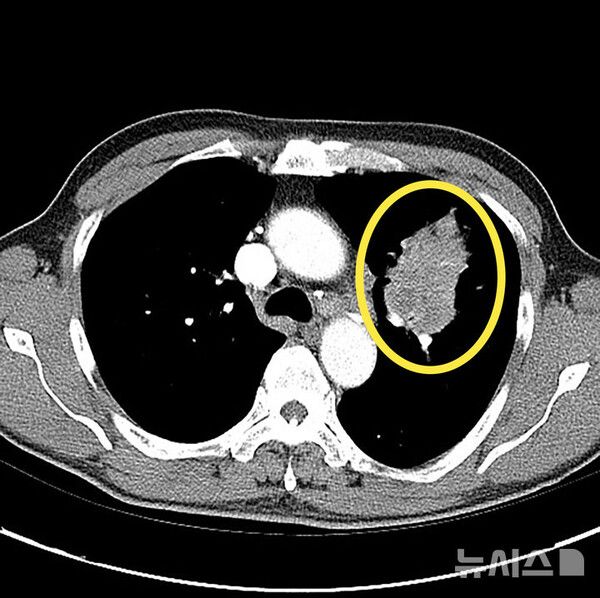

폐암은 초기 증상이 없는 경우가 대부분이고, 일반 감기와 증상이 비슷해 진단이 늦어지는 경우가 많다. 건강검진에서 우연히 결절이 발견돼 추가 검진을 통해 진단 되곤 한다.

15일 의료계에 따르면 폐암은 폐에 비정상적인 암세포가 무절제하게 증식해 종괴(덩어리)를 형성하고 인체에 해를 미치는 것을 말한다. 폐암은 폐에 국한돼 발견되기도 하지만 진행될 경우 반대쪽 폐뿐 아니라 임파선이나 혈액을 통하여 뼈, 간, 부신, 신장, 뇌, 척수 등 온몸으로 전이될 수 있다.

폐암이 조기 발견이 어려운 이유는 폐에는 감각 신경이 없어 통증을 잘 느끼지 않는 장기이기 때문이다. 실제 조기에 폐암이 진단되는 환자는 전체의 5~15%에 불과하다. 폐암이 진행되면 기침, 피 섞인 가래(객혈), 흉통, 호흡곤란, 체중감소 등이 나타날 수 있다. 하지만 이런 증상도 암이 꽤 진행된 후에야 나타나는 경우가 많아 증상만으로는 조기 진단이 어렵다. 증상이 나타났다면 이미 폐암이 어느정도 진행된 경우가 많다.

따라서 고위험군에서는 저선량 CT를 이용한 정기 검진이 매우 중요하다. 결절이 발견된다고 다 암으로 진행되는 것은 아니다. 결절은 암일 수도 있지만 염증, 섬유화, 림프절 비대, 과거 결핵 흔적 등 다양한 원인으로 생길 수 있다. 특히 폐암 고위험군이라면 호흡기알레르기내과 전문의에게 진료를 받아 정확한 평가를 받는 것이 필요하다.